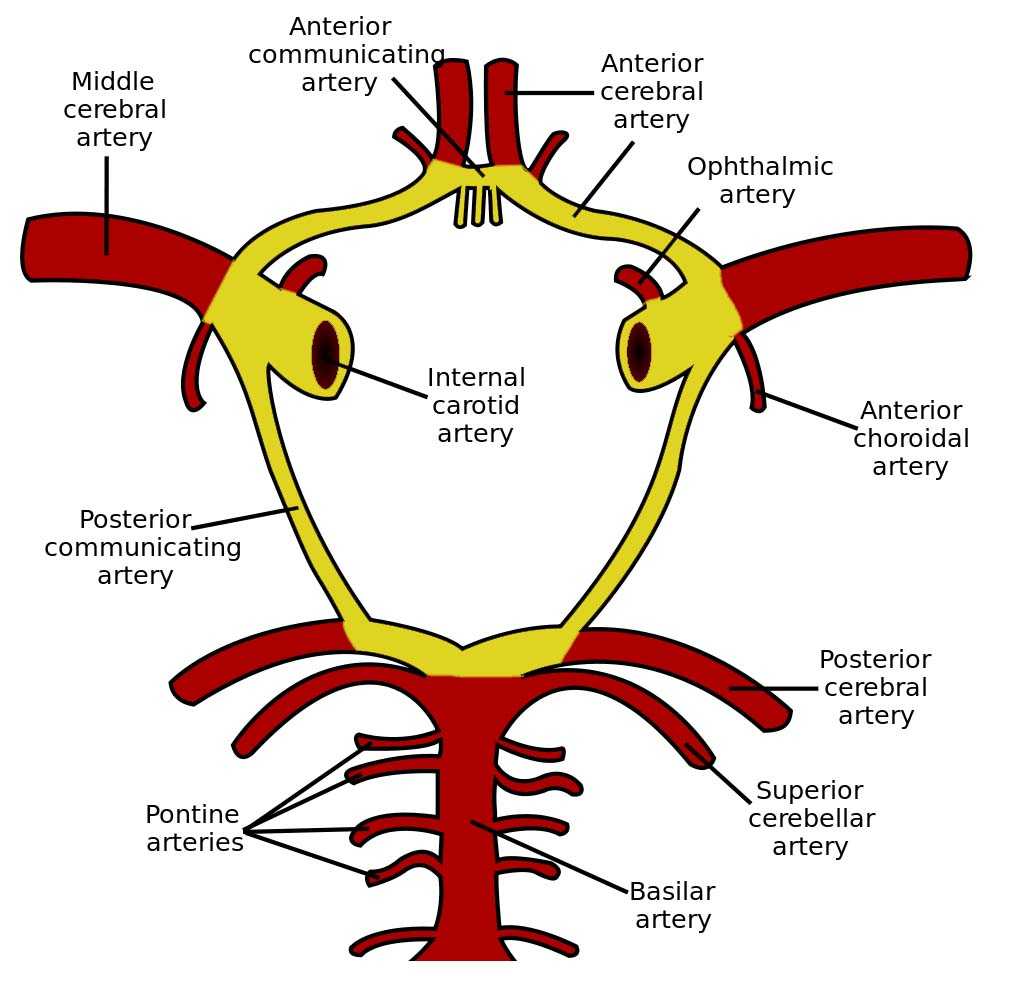

Cerebral arterial circle

Ophthalmic a.

- Dorsal nasal a.

- Supratrochlear a.

- Ant./ Post. ethmoid a.

- Supraorbital a.

- Ciliary a.

- Lacrimal a.

Internal carotid a.

- 進入carotid canal 前無分支

- CN X 伴行

- Carotid canal入顱

- carotid a. 夾 Stylopharyngeus m.(CN IX) , Styloglossus m. (CN XII)